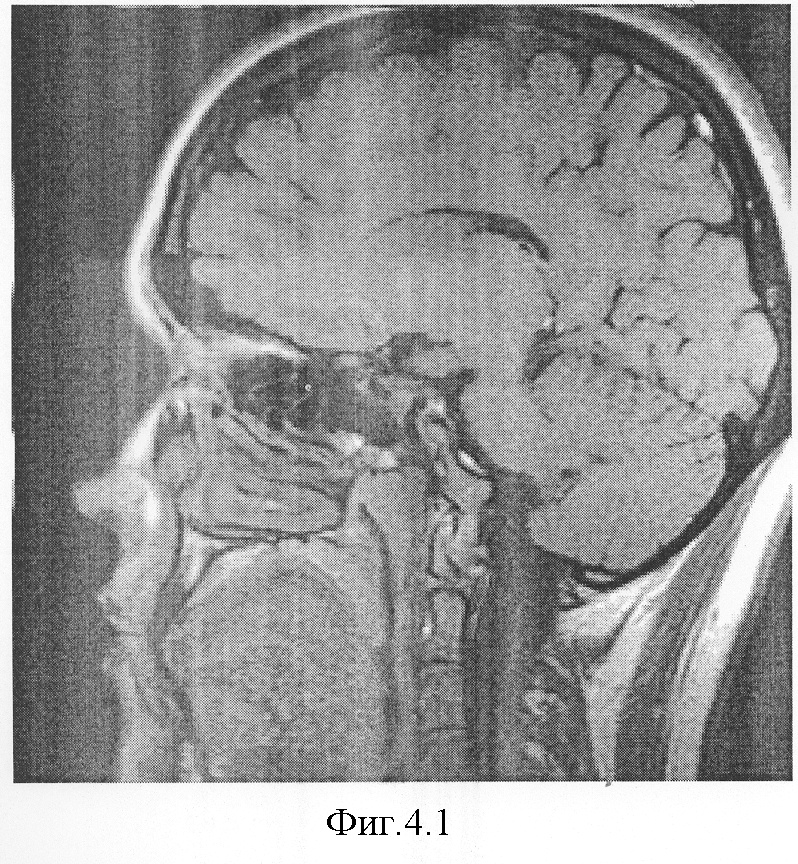

На фиг.4.1-7 показаны результирующие семь изображений, проходящие в сагиттальной плоскости через гипофиз. При этом фиг.4.1 проходит в непосредственной близости от турецкого седла справа, через сифон внутренней сонной артерии, гипофиз не затрагивает;